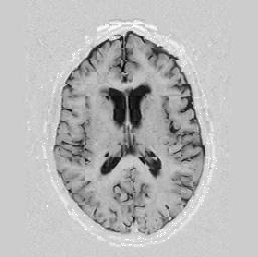

Lastly, Figure [*] shows 10 iterations at level 2, 6 iterations at level 1, and 6 at level 0.

Figure: Multi-scale NRR. From left to right, top then bottom: before NRR; after 10 iterations of NRR at level 2; after another 6 iterations of NRR at level 1; after 6 more iterations at level 0.